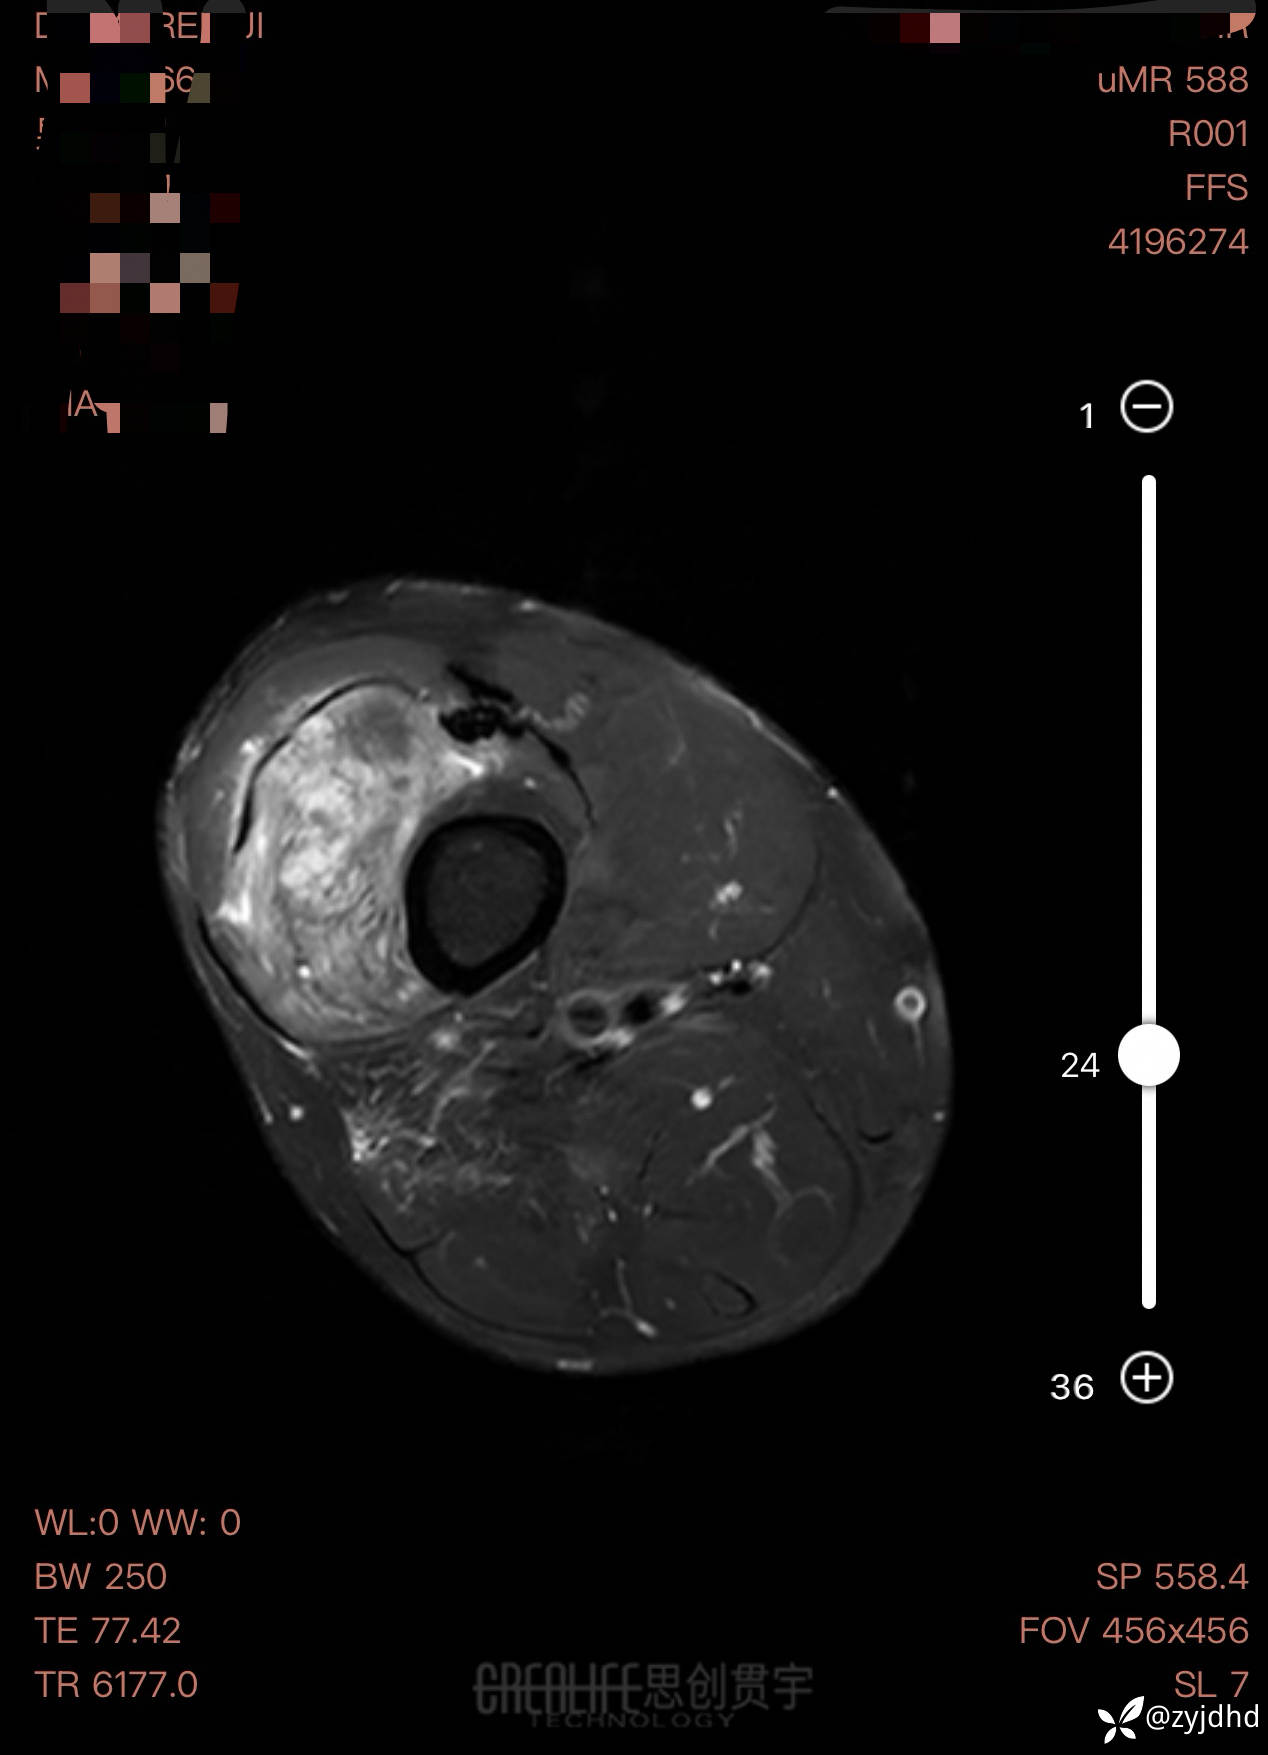

男性,发现右大腿肿物20年。

考虑什么诊断?治疗方案